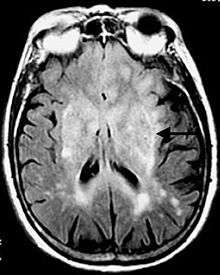

The pulse sequence is an inversion recovery technique that nulls fluids. For example, it can be used in brain imaging to suppress cerebrospinal fluid (CSF) effects on the image, so as to bring out the periventricular hyperintense lesions, such as multiple sclerosis (MS) plaques.[1]

- Multiple sclerosis (MS) plaques